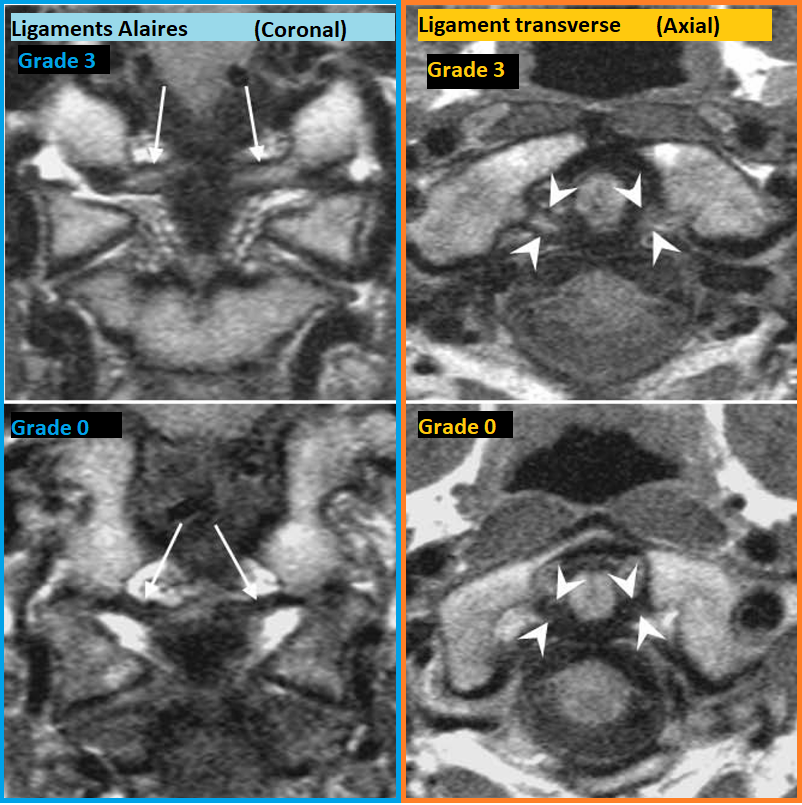

Alair alar ligament ligaments ligamentaires cervicale atlas atlanto occipitale axial axis atlantoaxial disruption rupture entorse lésion rupture déchirure dechiré antérieur postérieur jaune flavum hypersignal croix crux cruciforme alaires aliletes instable fracture